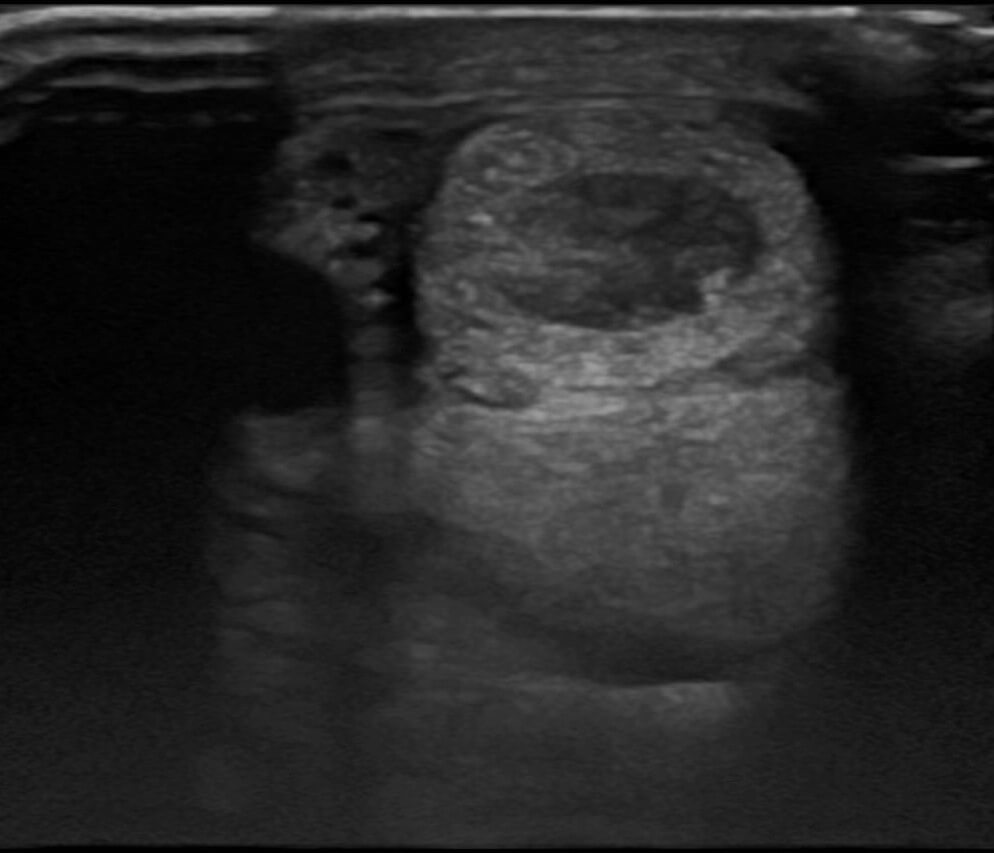

Ultraljudsbild av en skada i ytliga böjsenan, se det mörka området i den övre ovalen i bilden.

En senskada ger inflammation, ökad värme och svullnad. Mindre skador på senfibrerna ger en lindrig svullnad på benet, vilken känns varmare än motsvarande område på det andra benet. Dessa skador behöver inte alltid ge upphov till hälta, de kan därför missas om man inte dagligen känner igenom hästens ben. Vid mer omfattande skada ses ofta tydlig svullnad, ömhet och smärta samtidigt som hästen uppvisar hälta. Man använder ultraljud för att bedöma hur senan ser ut.